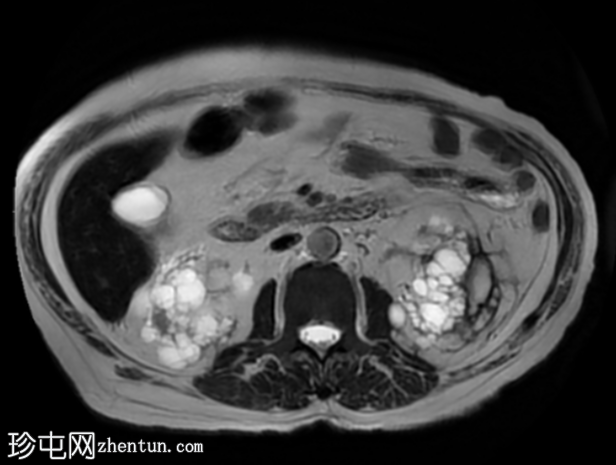

MRI

轴位

STIR序列

2.png

双侧肾囊性疾病,可见多个肾囊肿,其中许多呈复杂性(出血性)囊肿,T1加权像呈高信号,T2加权像呈低信号。

左侧可见一较大的肾周血肿,与上极出血性囊肿相连,提示出血性囊肿破裂(Wunderlich综合征)。

未见肾脏软组织肿块。

轻度肝脾肿大,受检骨骼T2加权像呈弥漫性低信号,提示肾性骨营养不良。